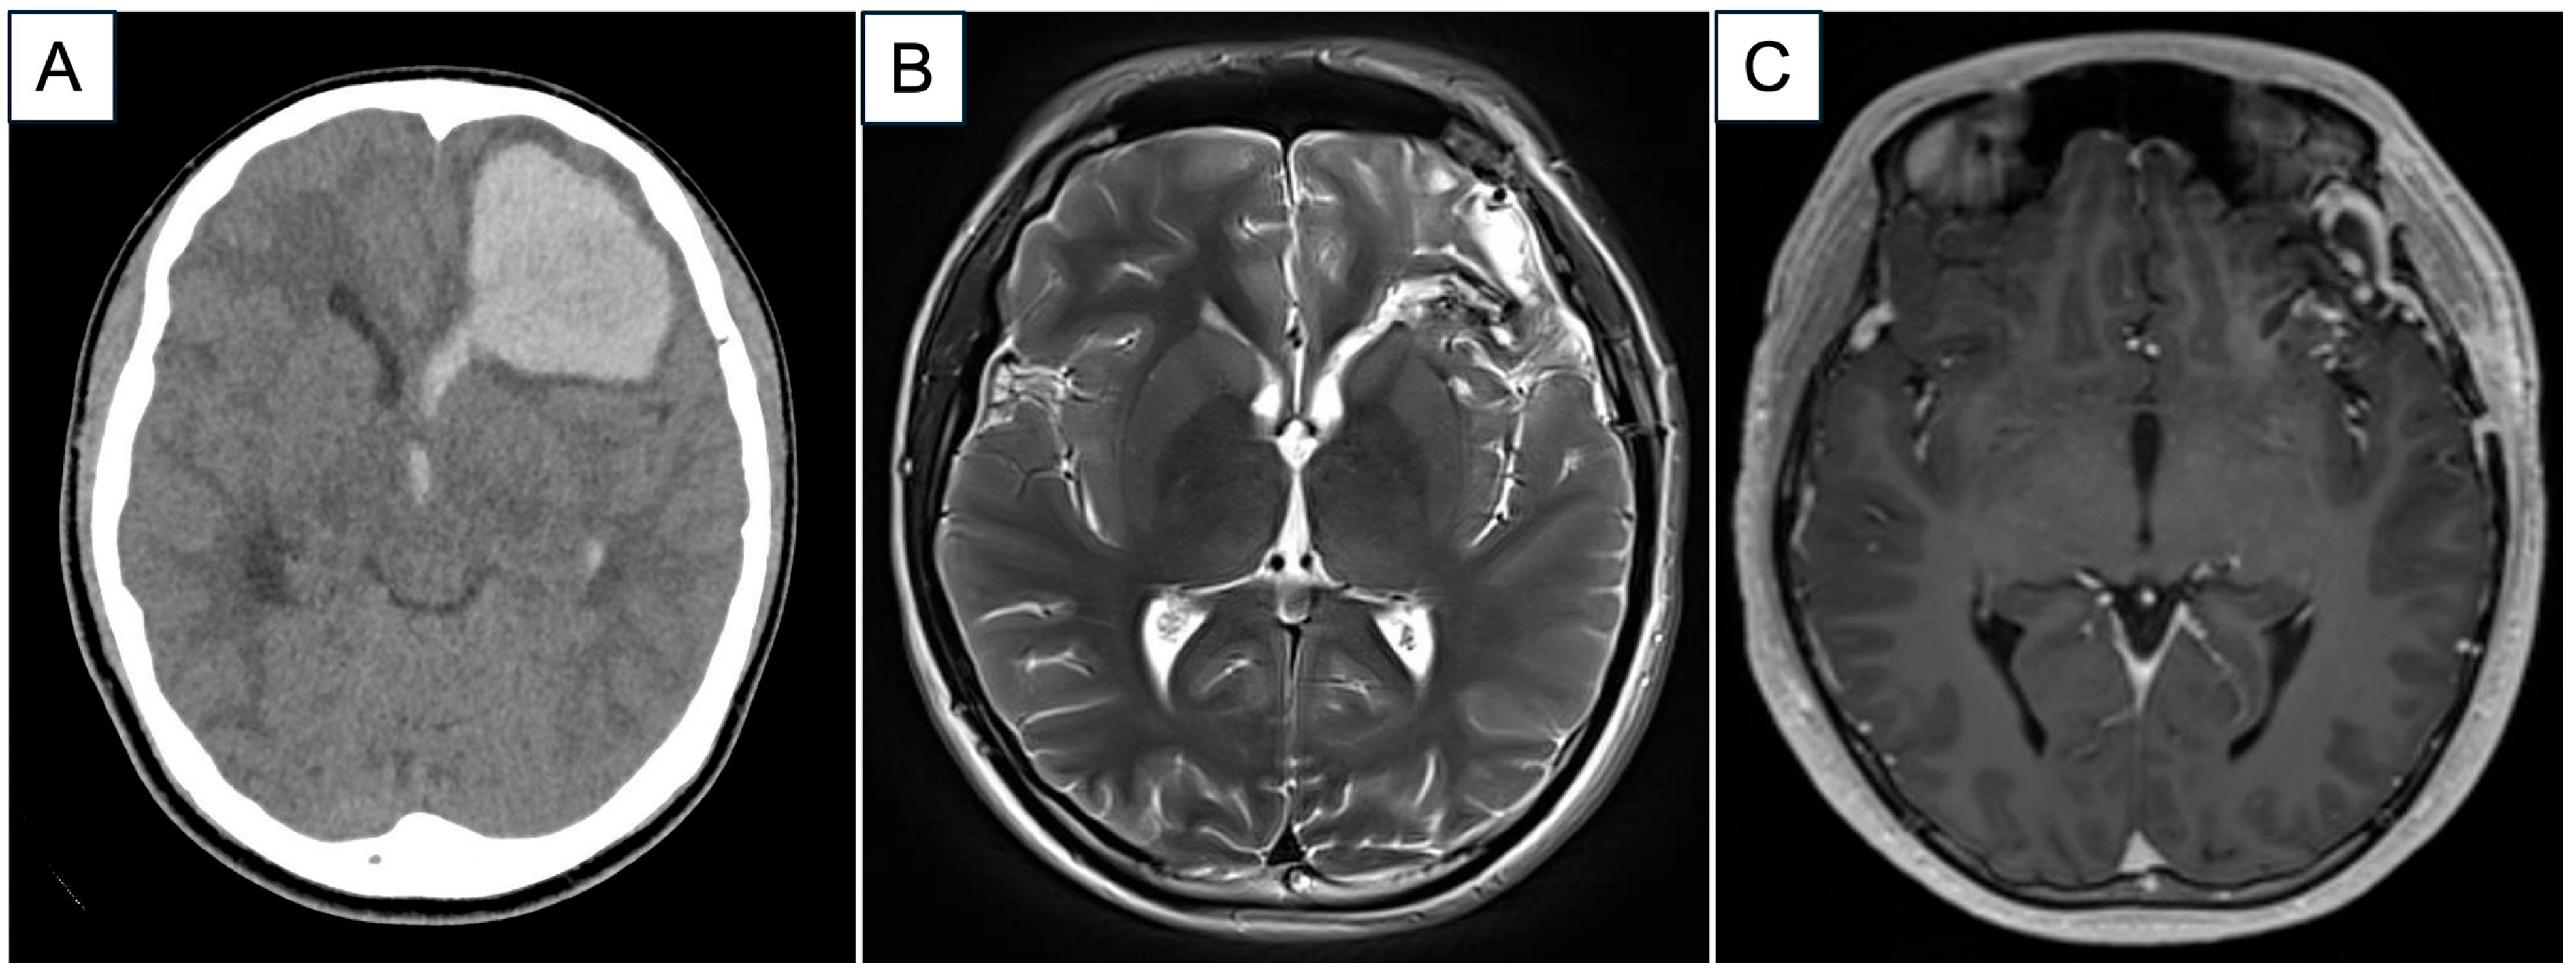

2. Case Report